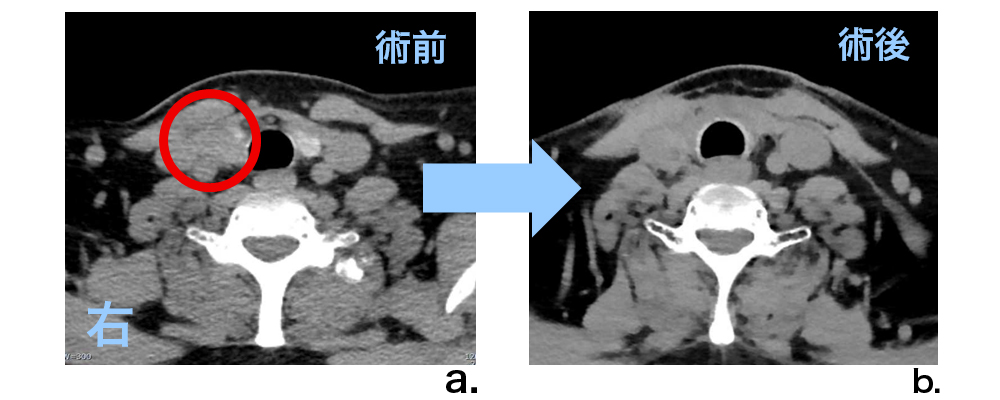

甲状腺癌を有する患者さんでは、甲状腺全摘を行った後にも画像診断では確認できない顕微鏡的潜在病巣がしばしば残存します。このため、再発予防としてI-131内用療法を加え、残存がん細胞を死滅させます。提示症例では、術前にみられたがん病巣を摘除後、CT画像では明らかな残存を指摘できなかったものの、I-131甲状腺シンチグラフィーでは摘除部位(甲状腺床と呼びます)に明らかなI-131の集積がみられ癌の残存が強く疑われます。取り込まれたI-131が発するβ線は、残存癌細胞に強力なダメージを与えます。本例では、その後再発を見ていません。

術前CT(画像a)では、甲状腺右葉に周囲組織に浸潤するがん病巣を認めます(赤丸○)。術後CT(画像b)では、画像上はっきりしたがん病巣残存を指摘できません。しかし、I-131甲状腺シンチグラム(画像c)では、甲状腺床(甲状腺摘除部位)に強い集積(スター状の黒い陰影を伴う中心部の黒い部分)がみられ、癌の残存が強く疑われます。集積したI-131が、そのまま抗がん作用を持つ治療薬となります。